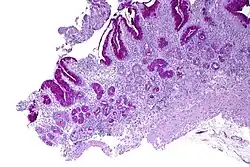

| Micrograph showing nodular enterochromaffin-like cell hyperplasia, as demonstrated with chromogranin A immunostaining, in the body of the stomach. Parietal cells are not readily apparent. These changes are in keeping with autoimmune metaplastic atrophic gastritis, a histologic correlate of vitamin B12 deficiency anemia. | |

PA may be considered as an end stage of autoimmune atrophic gastritis, a disease characterised by stomach atrophy and the presence of antibodies to parietal cells and intrinsic factor.[38][39] Autoimmune atrophic gastritis, is localised to the body of the stomach, where parietal cells are located.[36] Antibodies to intrinsic factor and parietal cells cause the destruction of the oxyntic gastric mucosa, in which the parietal cells are located, leading to the subsequent loss of intrinsic factor synthesis. Without intrinsic factor, the ileum can no longer absorb the B12.[40] Atrophic gastritis is often a precursor to gastric cancer.[39]

The diagnosis of atrophic gastritis type A should be confirmed by gastroscopy and stepwise biopsy.[59] About 90% of individuals with PA have antibodies for parietal cells; however, only 50% of all individuals in the general population with these antibodies have pernicious anemia.[60]